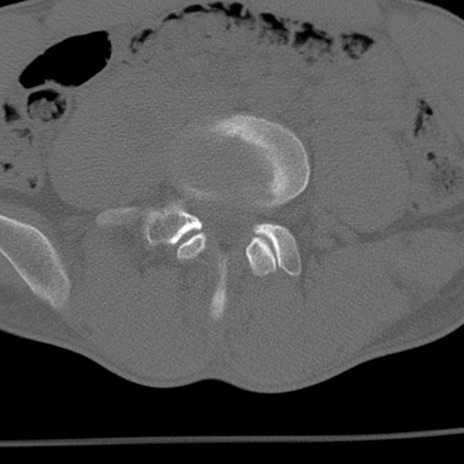

症例3 腰椎CT(横断像)

腰椎CT